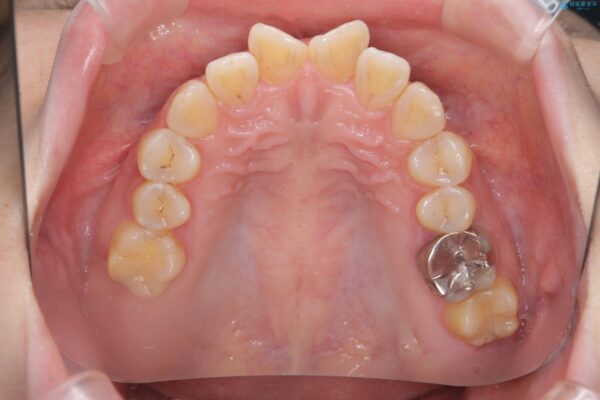

治療後

傾いた前歯、インビザラインで改善 治療後画像 傾いた前歯、インビザラインで改善 治療後画像 傾いた前歯、インビザラインで改善 治療後画像 傾いた前歯、インビザラインで改善 治療後画像